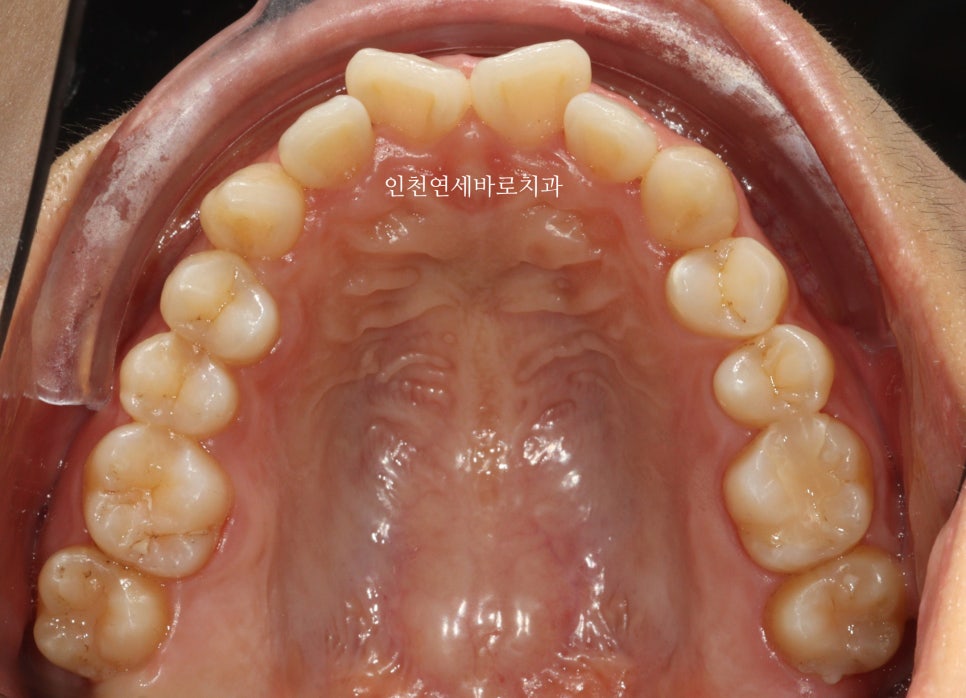

삐뚤삐뚤한 앞니를 고치고 싶어오셨습니다

인비절라인 라이트로 진행하기로 하고 장치 제작을 했습니다.

전후 비교입니다